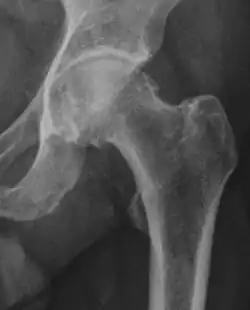

X-ray

Projectional radiography ("X-ray") is often considered first line for FAI.[10] Anterior-posterior pelvis and a lateral image of the hip in question should be attained.[10] A 45-degree Dunn view is also recommended.[10][19]

| Alpha angle | ![]() |

Degree of bulging of the femoral head-neck junction: In normal conditions there is a symmetric concave contour at the junction of the femoral head and neck. Loss of this concavity or bone bulging may lead to cam type impingement. The degree of this deformity can be measured by the alpha angle. Although it can be measured in the cross-lateral view, the 45° Dunn view is considered more sensitive and the frog leg view more specific in determining pathologic values. |

|